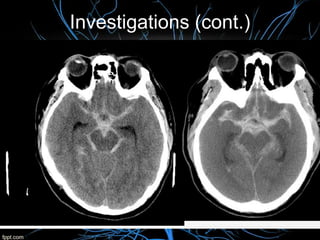

Rapid neuroimaging with CT or MRI is recommended to distinguish ischemic stroke from

ICH (Class I; Level of Evidence A)

For diagnosing ischemic stroke in the emergency setting:

CT scans (without contrast enhancements):

sensitivity= 16%specificity= 96%

MRI scan:

sensitivity= 83%specificity= 98%

For diagnosing hemorrhagic stroke in the emergency setting:

sensitivity= 89%specificity= 100%